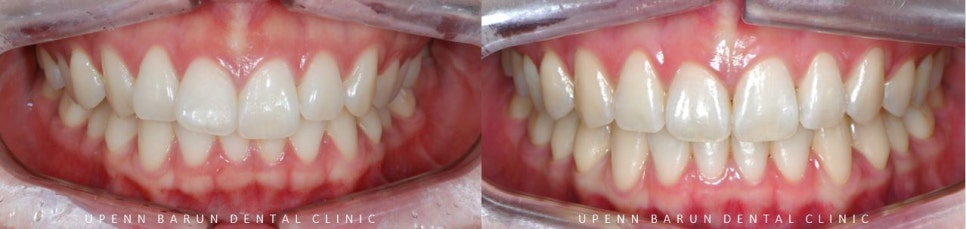

교정 전 후를 비교해보니

교정 전

윗니가 아랫니를 과도하게 덮고 있어

답답해 보였던 치아들이

교정 완료 후

과개교합이 개선되고

아랫니들이 더 잘 보이면서 시원해 보이는 느낌을 줍니다.

또한,

정중선이 일치하면서

치아들이 올바르게 배열된 모습을

확인해 보실 수 있습니다.